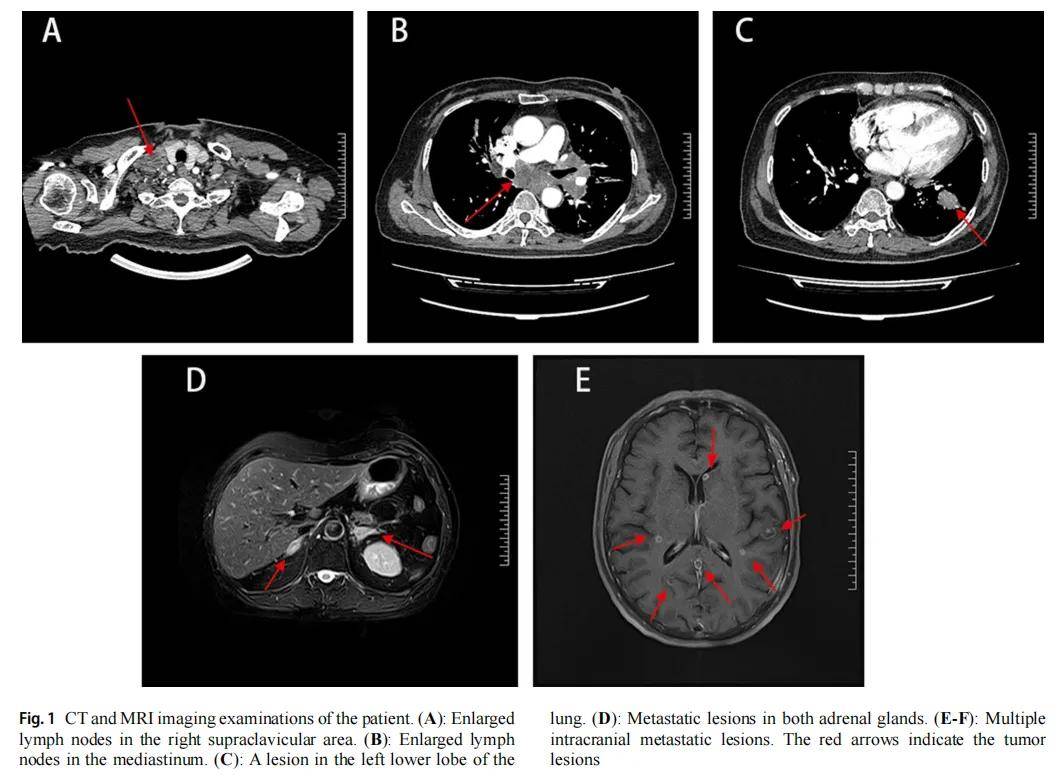

EGFR 19号外显子缺失和21号外显子点突变是肺腺癌中最常见的突变类型,携带此类突变的患者可从EGFR酪氨酸激酶抑制剂(TKIs)治疗中获得显著临床获益。然而,TKIs在罕见复合型EGFR突变中的疗